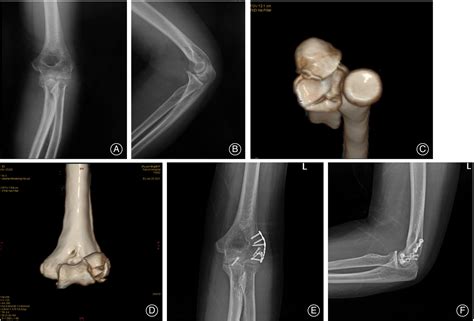

Diagnosis usually begins with a physical examination to test the stability of the elbow. However, because the coronoid is tucked deep within the joint, traditional X-rays may miss subtle fractures. A CT scan is often the gold standard for providing a 3D reconstruction of the ulnar coronoid process, allowing surgeons to see the exact size and orientation of a fracture fragment.

2. Surgical Fixation: If the fracture is large or causes significant joint instability (often referred to as the "terrible triad" of the elbow), surgery is required. This involves using plates, screws, or sutures to restore the bone's anatomy and reattach ligaments.